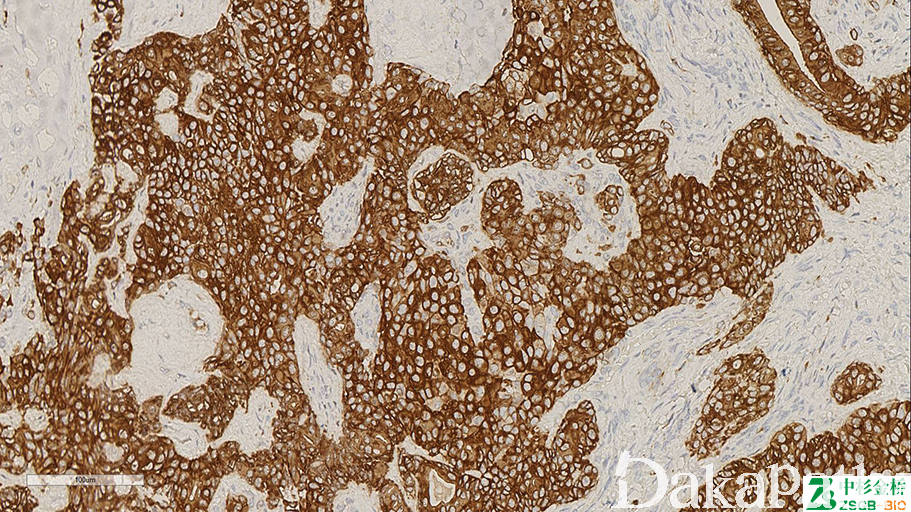

34βE12

别名: anti-cytokeratin K903 、CK904

高分子量角蛋白,与细胞角蛋白 1、5、10、14 反应。表达于鳞状上皮、腺体基地细胞等细胞的胞质

信号定位: 胞质